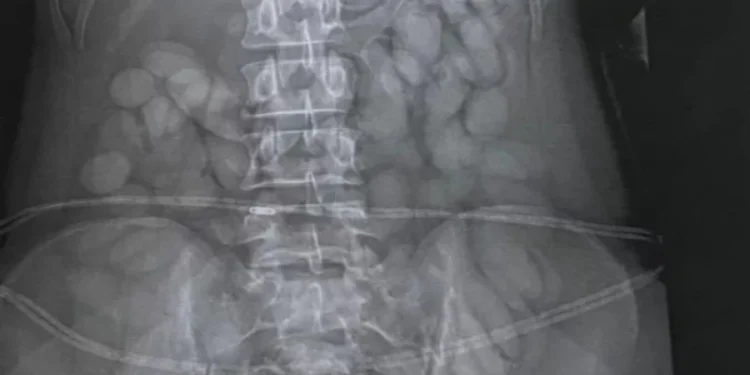

Μάλιστα, το «σκανάρισμα» του αεροδρομίου αποκάλυψε και την κρυψώνα της. Οι αστυνομικοί διαπίστωσαν ότι είχε καταπιεί δεκάδες «σφαίρες κοκαΐνης», με αποτέλεσμα να σταλθεί εσπευσμένα στο νοσοκομείο της πόλης για πλύση στομάχου. Εκεί, οι γιατροί διαπίστωσαν ότι η 30χρονη είχε καταβροχθίσει πάνω 60 «σφαιρίδια» ναρκωτικών.

Η εκπρόσωπος της εθνικής αστυνομίας Brig Athlenda Mathe ανέφερε: «Η ομάδα μας εντόπισε αμέσως το βαποράκι καθώς περνούσε από τη μεταναστευτική υπηρεσία. Συνελήφθη αμέσως, μεταφέρθηκε σε τοπικό νοσοκομείο όπου μια ιατρική ακτινογραφία εντόπισε ξένα αντικείμενα στο στομάχι της».